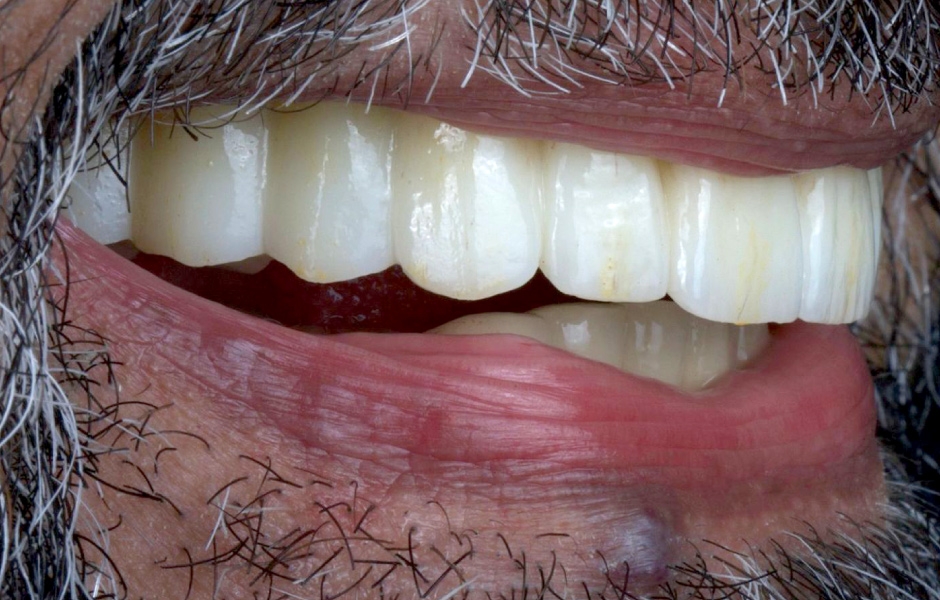

Definitivní náhrada byla nasazena a ověřena z hlediska estetiky, okluze a funkce (obr. 51–55). Panoramatický kontrolní snímek potvrdil, že všechny parametry protetického ošetření odpovídají očekávaným hodnotám (obr. 56).

Při kontrole po 18 měsících po dokončení ošetření bylo provedeno intraorální, extraorální a radiografické vyšetření. Nebyly zjištěny žádné patologické nálezy a výsledné parametry zůstaly stabilní (obr. 57–62).

Obr. 51

Obr. 52

Obr. 53

Obr. 54

Obr. 55